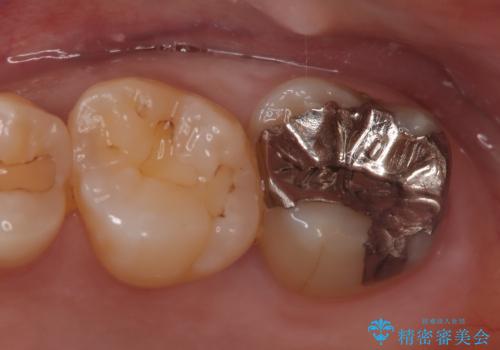

[ オールセラミッククラウン ] すき間の目立つ前歯をきれいにしたい!

担当医 大元洋佑